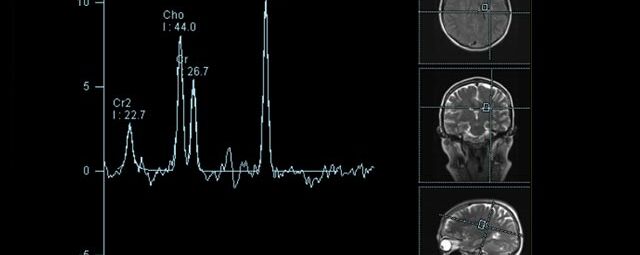

• MR-Spektroskopie

Diese Untersuchung führen wir ausschließlich an unserem Standort in Leipzig am Diakonissenkrankenhaus durch. Bitte nehmen Sie zur Vereinbarung eines Termins telefonischen Kontakt mit uns auf: 0341 3937-3000 oder schreiben Sie uns eine E-Mail an: